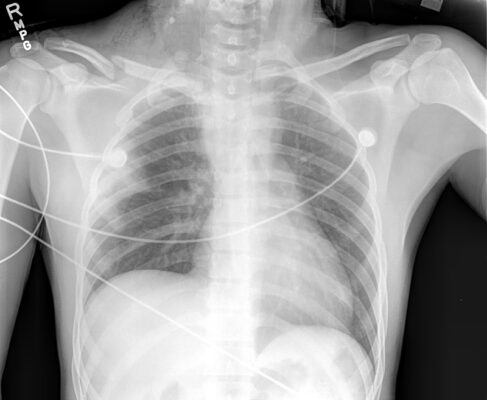

- Hình ảnh học: MRI (ưu tiên), Chụp tuỷ đồ CT (trẻ em, xác định bong rễ thần kinh), siêu âm (khối u), X quang phổi (liệt cơ hoành chứng tỏ tổn thương dây thần kinh phế vị kèm theo).